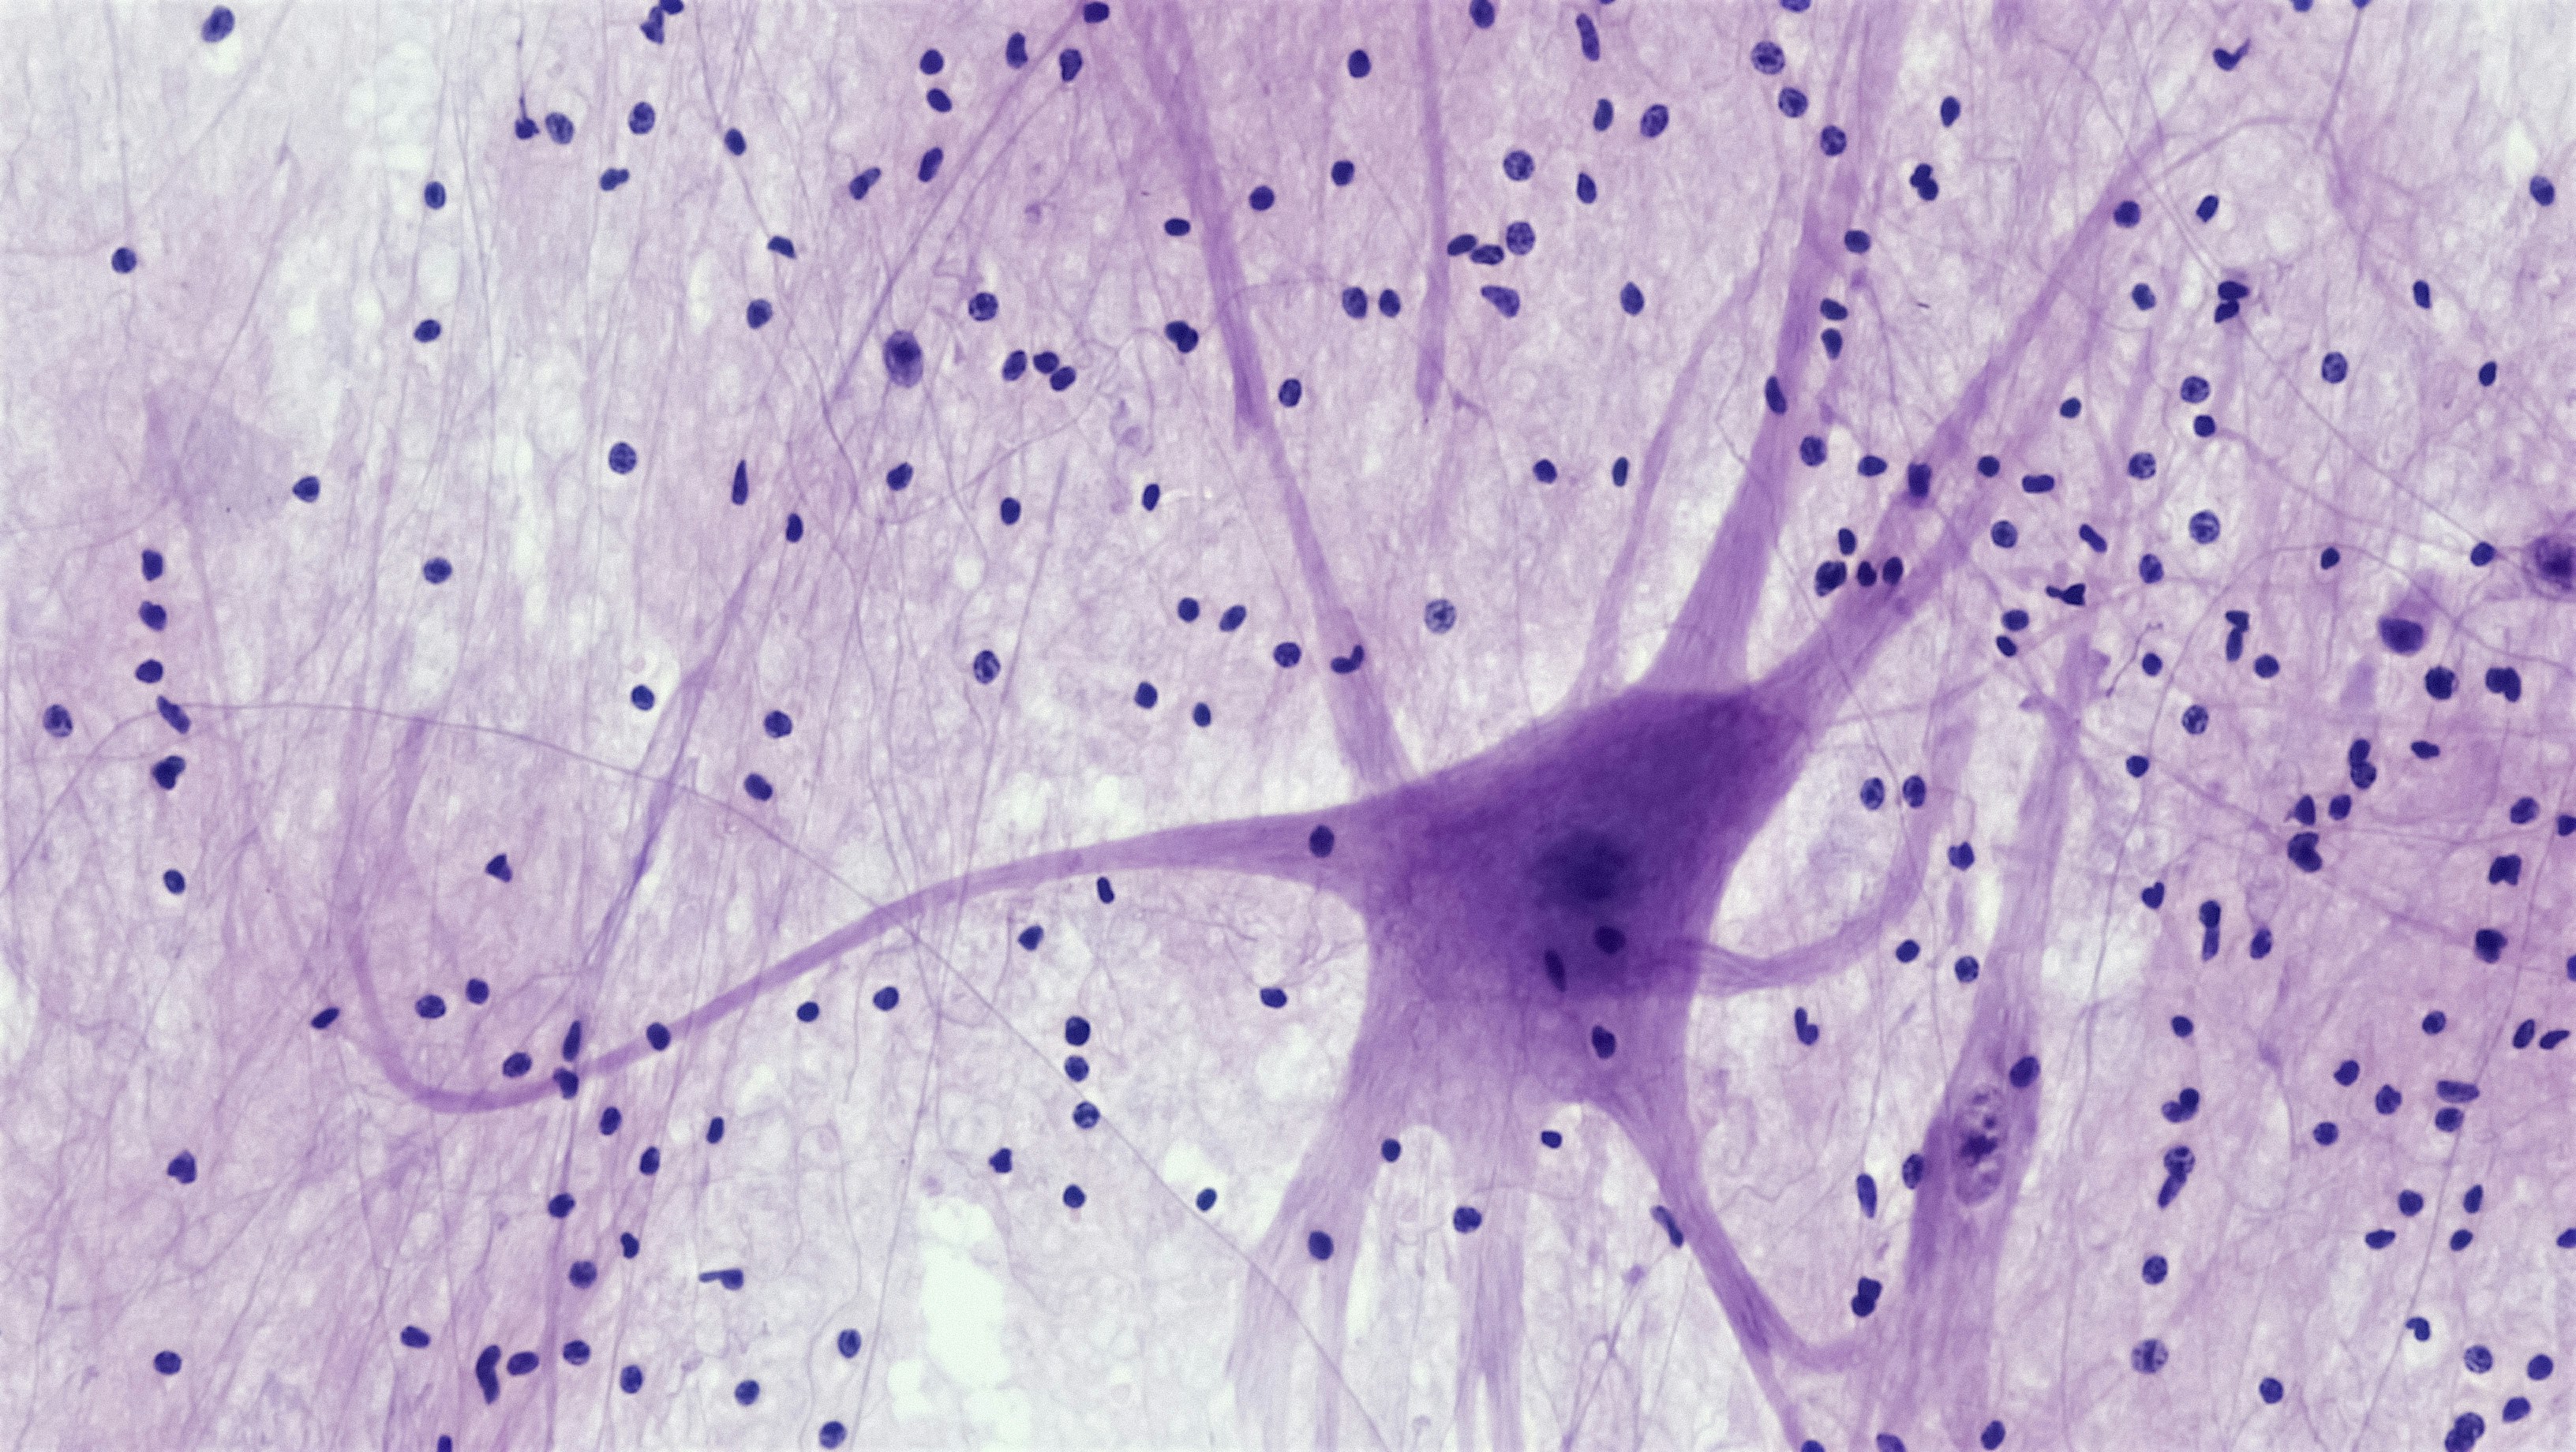

Descubre cómo las redes neuronales pueden optimizar el rendimiento máximo en diferentes ámbitos. Aprende cómo esta tecnología puede potenciar tus resultados de forma eficiente y efectiva.